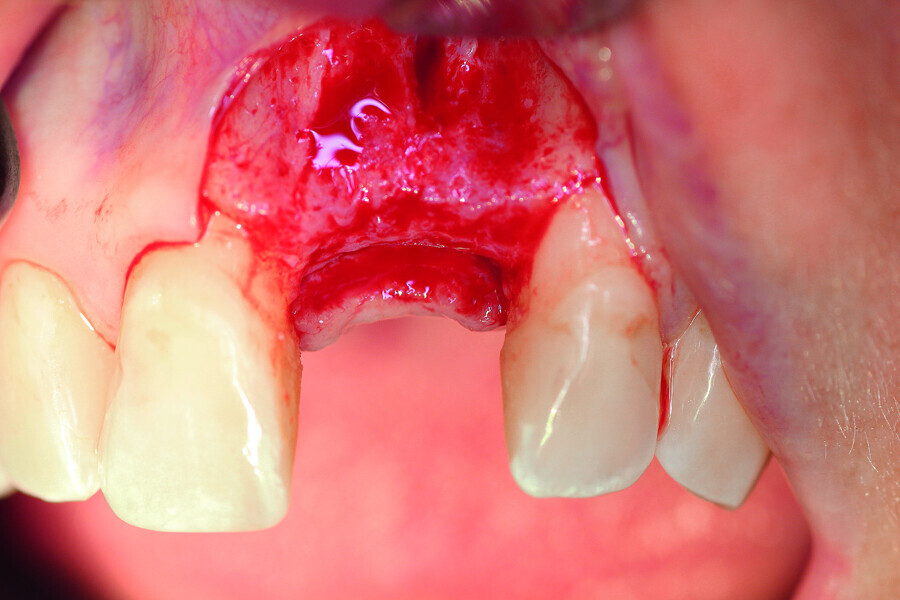

Fig. 6a: Transversal bone augmentation was performed.

Fig. 6b: Transversal bone augmentation was performed.